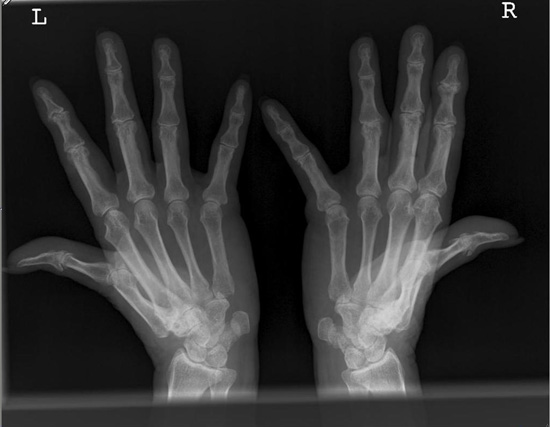

Hand / Handgelenk

Norgaard

Das Grundgelenk des rechten Daumens ist in der Norgaard-Aufnahme nicht gut einsehbar. Es wird teils vom Metacarpalen 2 überlagert. Die Daumen wurden bzw. könnten nicht genügend nach außen gestreckt werden.

Abhilfe

Bei solchen Patienten, die Probleme haben die Daumen mit eigener Kraft nach außen zu "biegen", sollte man mit Klebestreifen (Leukosilk) nachhelfen und die Daumen nach außen ziehen. Aber auch nur so weit wie es der Patient toleriert.